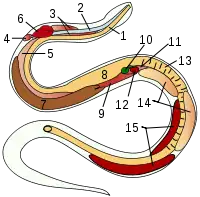

Vertebrates

- esophagus

- trachea

- tracheal lungs

- rudimentary left lung

- right lung

- heart

- liver

- stomach

- air sac

- gallbladder

- pancreas

- spleen

- intestine

- testicles

- kidneys